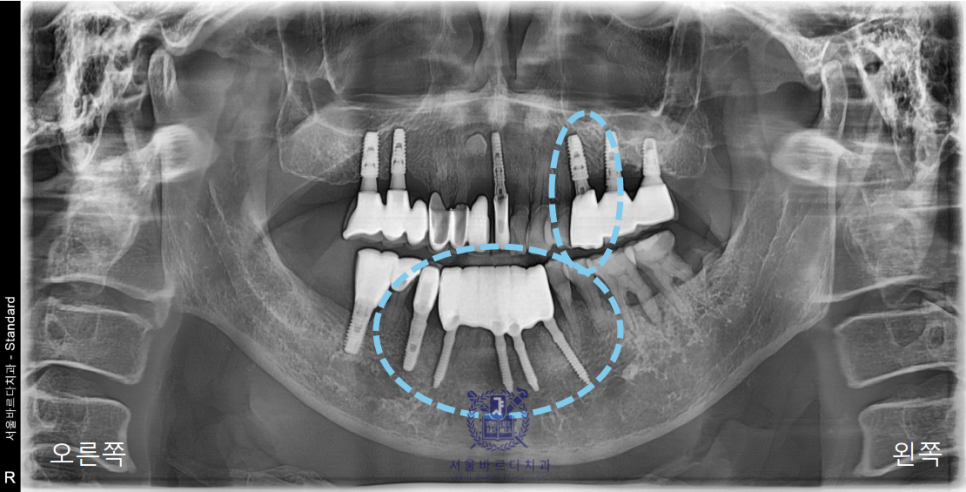

앞니가 많이 붓더니 한참을 아프다가 흔들리기 시작했다고하셔서

일단 파노라마 사진을 찍어 전체적인 상태를 체크해드렸습니다.

이미 다수의 보철과 임플란트를 하셨고,

앞니쪽은 조금 더 자세하게 보기위해 치근단 엑스레이를 추가로 촬영하였습니다.

양쪽 송곳니 두개를 이용해 앞니 6개의 보철을 사용하고계셨는데

지지해주던 양쪽 송곳니쪽에 문제가 생겨서

염증이 이미 많이 진행된 상태였습니다.

문제가 생긴 아래 앞니 부분은 이미 신경치료도 다 되어있는 상태였는데도

다시 뿌리 끝까지 염증이 생겨 결국 치아까지 많이 흔들리고,

환자분의 통증과 불편감이 상당했기에 충분한 상담을 통해

발치 후 임플란트를 하는 것으로 방향을 잡아드렸습니다.

전체적으로 치주염도 심한 상태였고

왼쪽 위 역시 앞니처럼 한참 고생하시다가

발치한지 얼마 안된 상태라고 하셨습니다.

아래 앞니는 6개의 치아를 안정적으로 유지할 수 있는

견고한 4개의 뿌리를 식립하였고

왼쪽 위는 큰어금니 다음으로 중요한 역할을 수행할 작은

어금니에 맞는 사이즈로 식립하였습니다.